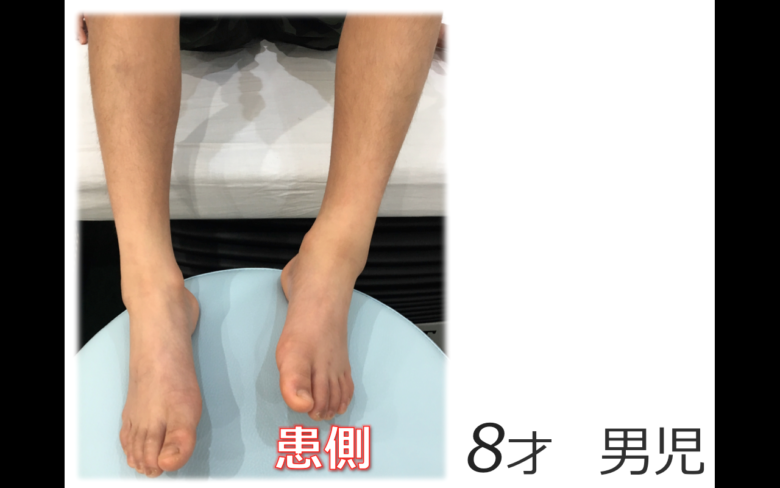

子供さんの足首の骨折

子供さんの足首の骨折

子供さんの足首の骨折